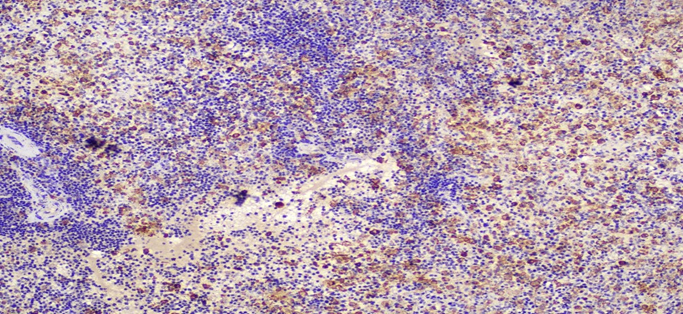

Figure 6A: Photomicrographs highlighting macrophages in lymph node stained with CD68 (IHC, 20X magnification).

Figure 6B: Photomicrographs highlighting macrophages in lymph node stained with CD163 (IHC, 20X magnification).

Figure 6C: Photomicrographs highlighting macrophages in spleen stained with CD68 (IHC, 10X magnification).

Figure 6D: Photomicrographs highlighting macrophages in spleen stained with CD163 (IHC, 10X magnification).

Figure 7A: Photomicrograph highlighting macrophages in bone marrow stained with CD61 (IHC, 20X magnification).

Figure 7B: Photomicrograph highlighting macrophages in bone marrow stained with CD68 (IHC, 20X magnification).

Figure 7C: Photomicrograph highlighting macrophages in bone marrow stained with CD163 (IHC, 20X magnification).

Lymph Nodes: Paracortical expansion with numerous histiocytes actively phagocytosing hematopoietic elements. Hemophagocytic cells highlighted with CD68 and CD163.

Bone Marrow: Hypercellular marrow (70% cellularity) with trilineage hematopoiesis. Many hemophagocytic cells are identified. Trabecular bone is unremarkable. CD68 and CD163 highlights hemophagocytic activity. CD61 highlights megakaryocytes. Iron: minimal iron storage; could be suboptimal due to decalcification of bone.